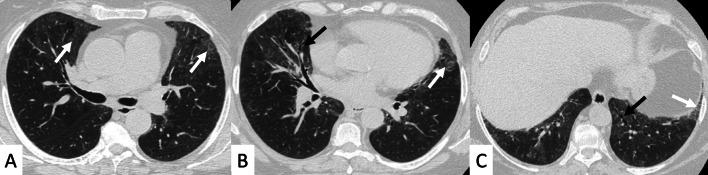

Connective tissue diseases (CTDs) include a spectrum of disorders that affect the connective tissue of the human body; they include autoimmune disorders characterized by immune-mediated chronic inflammation and the development of fibrosis. Lung involvement can be misdiagnosed, since pulmonary alterations preceded osteo-articular manifestations only in 20% of cases and they have no clear clinical findings in the early phases. All pulmonary structures may be interested: pulmonary interstitium, airways, pleura and respiratory muscles. Among these autoimmune disorders, rheumatoid arthritis (RA) is characterized by usual interstitial pneumonia (UIP), pulmonary nodules and airway disease with air-trapping, whereas non-specific interstitial pneumonia (NSIP), pulmonary hypertension and esophageal dilatation are frequently revealed in systemic sclerosis (SSc). NSIP and organizing pneumonia (OP) may be found in patients having polymyositis (PM) and dermatomyositis (DM); in some cases, perilobular consolidations and reverse halo-sign areas may be observed. Systemic lupus erythematosus (SLE) is characterized by serositis, acute lupus pneumonitis and alveolar hemorrhage. In the Sjögren syndrome (SS), the most frequent pattern encountered on HRCT images is represented by NSIP; UIP and lymphocytic interstitial pneumonia (LIP) are reported with a lower frequency. Finally, fibrotic NSIP may be the interstitial disease observed in patients having mixed connective tissue diseases (MCTD). This pictorial review therefore aims to provide clinical features and imaging findings associated with autoimmune CTDs, in order to help radiologists, pneumologists and rheumatologists in their diagnoses and management.

结缔组织病(CTDs)包括一系列影响人体结缔组织的疾病;它们包括以免疫介导的慢性炎症和纤维化发展为特征的自身免疫性疾病。肺部受累可能会被误诊,因为肺部改变仅在20%的病例中先于骨关节炎表现出现,且在早期阶段没有明确的临床发现。所有肺部结构都可能受累:肺间质、气道、胸膜和呼吸肌。在这些自身免疫性疾病中,类风湿关节炎(RA)的特征是普通型间质性肺炎(UIP)、肺结节和伴有空气潴留的气道疾病,而系统性硬化症(SSc)常表现为非特异性间质性肺炎(NSIP)、肺动脉高压和食管扩张。NSIP和机化性肺炎(OP)可见于多发性肌炎(PM)和皮肌炎(DM)患者;在某些情况下,可观察到小叶周围实变和反晕征区域。系统性红斑狼疮(SLE)的特征是浆膜炎、急性狼疮性肺炎和肺泡出血。在干燥综合征(SS)中,HRCT图像上最常见的表现是NSIP;UIP和淋巴细胞间质性肺炎(LIP)的报道频率较低。最后,纤维化NSIP可能是混合性结缔组织病(MCTD)患者中观察到的间质性疾病。因此,本图像综述旨在提供与自身免疫性CTDs相关的临床特征和影像学表现,以帮助放射科医生、呼吸科医生和风湿病科医生进行诊断和管理。